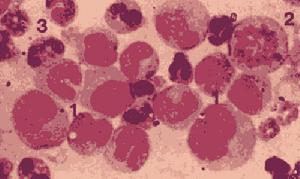

肥大細胞白血病患者一般有貧血、血小板減少;白細胞總數(10—15)x109/L,肥大細胞占5%~90%。骨髓活檢示肥大細胞明顯增多,有時可達90%(26.2%—91.8%),白血病性肥大細胞呈圓形或類圓形,染色質較細緻,核仁清或不清,胞漿藍色、充滿或多或少的深紫紅色顆粒並覆蓋於核上,並易見偽足和吞噬紅細胞現象。MCL的肥大細胞超微結構:核1個或多個,偶見明顯核仁。細胞漿中含有線粒體、脂質體,顆粒內容物缺乏或顆粒中充滿小粒子及典型的捲軸樣特徵。A顆粒可見,嗜鹼粒細胞的0粒不見。